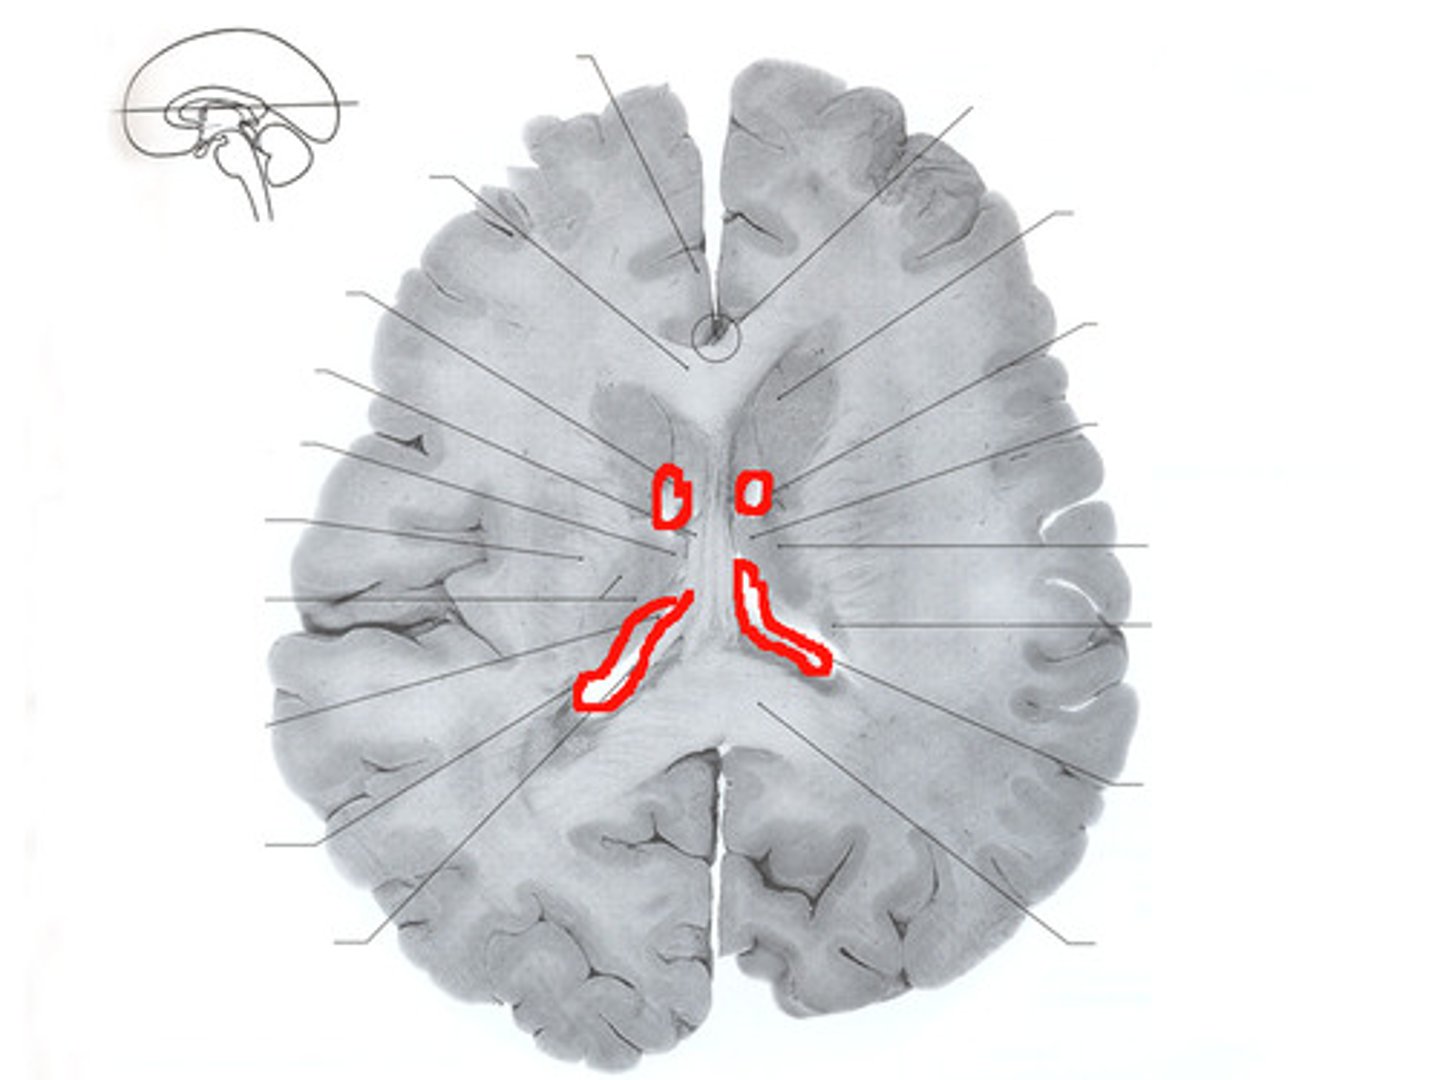

Cerebral Cortex (surface)

Cerebral White matter

Choroid Plexus

Right Lateral Ventricle

Choroid PLexus of the third ventricle

Interventricular Foramen

third ventricle

Basal Nuclei (ganglia)